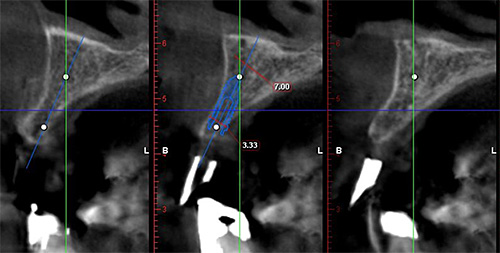

CTデータをもとに、インプラントの埋入をシミュレーションし、精密な計画を立てます。前歯のインプラントで難しいのは、埋入位置が0,5mmと狂うと取り返しがつきません。